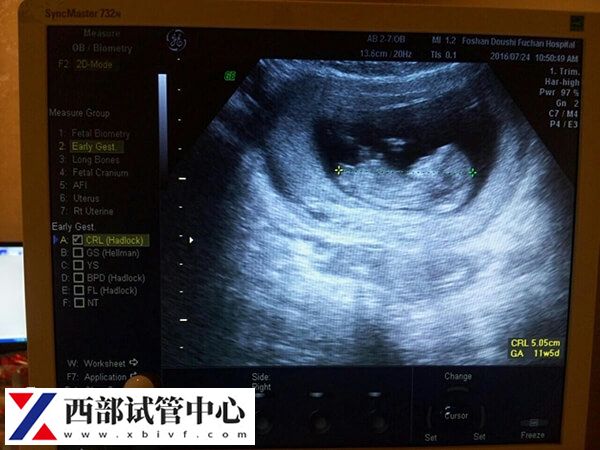

移植周期后若是成功妊娠,首先要恭喜你已成功晋级准妈的行列。建议在两个时间点来进行超声检查,需要对临床妊娠进行评估,及时发现病理情况并及时处理,避免出现不良的后果,如宫外孕、多胎妊娠、胚胎停滞发育等。

- 胚胎移植后4周左右(也就是临床上大家常听到的一超),目的是了明确妊娠部位、胎儿个数、发育状况及有无胎心搏动;

- 胚胎移植后7~8周左右(俗称二超),目的是明确了解宫内胎儿发育情况,如果是双胎妊娠,需要明确双胎的性质,为您更好的随访胎儿发育提供依据。